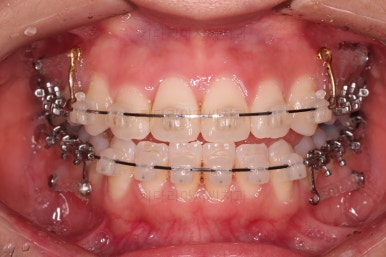

부산교정잘하는치과 초진 시 입안의 모습입ㄴ디ㅏ.

맞물림은 크게 나쁜 편은 아니었고요.

앞니 쪽이 위아래가 다 삐뚤고, 위에 작은 앞니 하나가 거꾸로 물리는 상태였습니다.

거꾸로 물리는 상황에서 특히 아래 앞니는 점점 잇몸이 꺼지는 증상이 생기면서 장기적인 치아의 수명에 영향을 주게 됩니다.